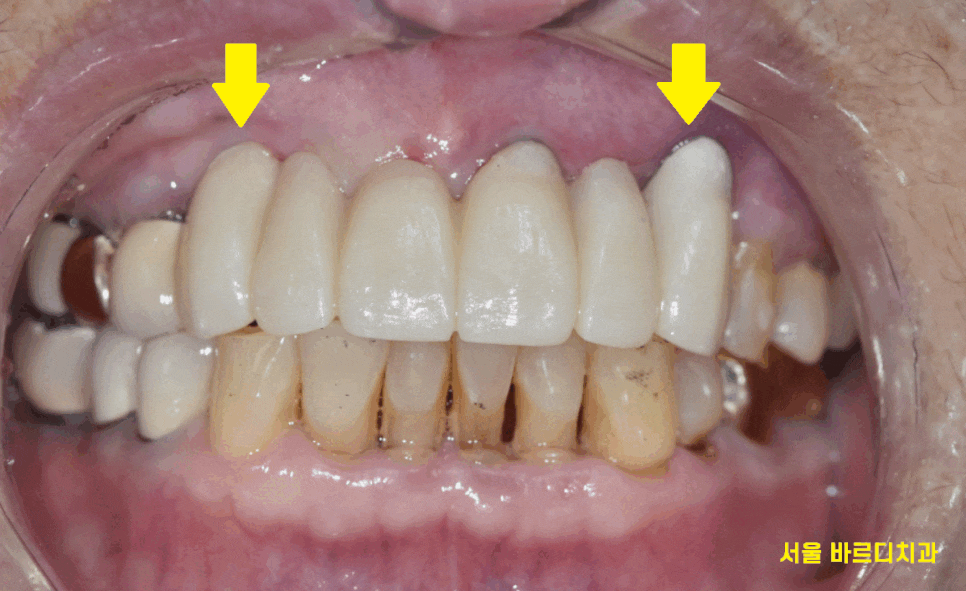

송곳니부터 송곳니까지

앞니 6개를 묶어놓은 형태로 치료를 하셨더라고요~

24.03.06

눈으로 보기에는 참으로 아름답지만 말이죠.

치아는 문제가 많았습니다.

충치가 많이 먹은 송곳니

기둥까지 넣어 보강한 치아의 실금

양쪽 송곳니 두개 다 문제가 있었습니다.

24.07.31

6개의 앞니 임플란트 브릿지로 완성해드렸습니다.